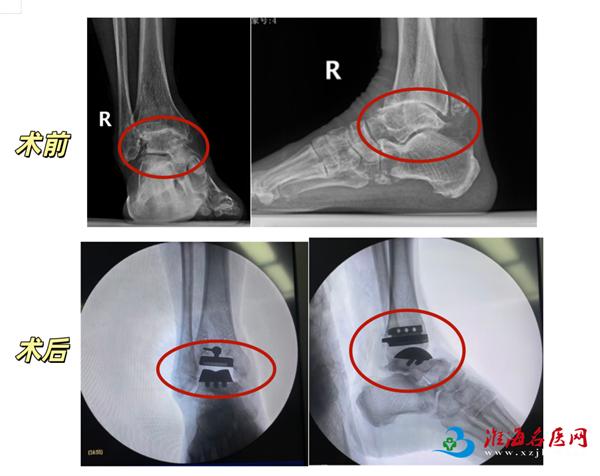

团队融入精准微创理念,在术前利用三维CT影像数据进行个体化设计,并借助3D打印技术制作了手术导板,以实现假体的精准安放。术中,医生在有效清除病变组织的同时,尽可能保护了关节周围重要的韧带和软组织,为术后关节的稳定性与功能恢复打下了基础。得益于精准的术前规划和微创的手术操作,患者术后得以在专业指导下早期开始康复锻炼,缩短了恢复周期。

术后3—4周,两位患者踝关节疼痛已显著减轻,可正常活动。

资料图

简单来说,全踝关节置换术就是通过手术将受损的踝关节软骨和部分骨组织替换为人工假体,模拟正常踝关节的结构和功能,从而彻底解除疼痛、矫正畸形、恢复关节活动度的一种微创手术。